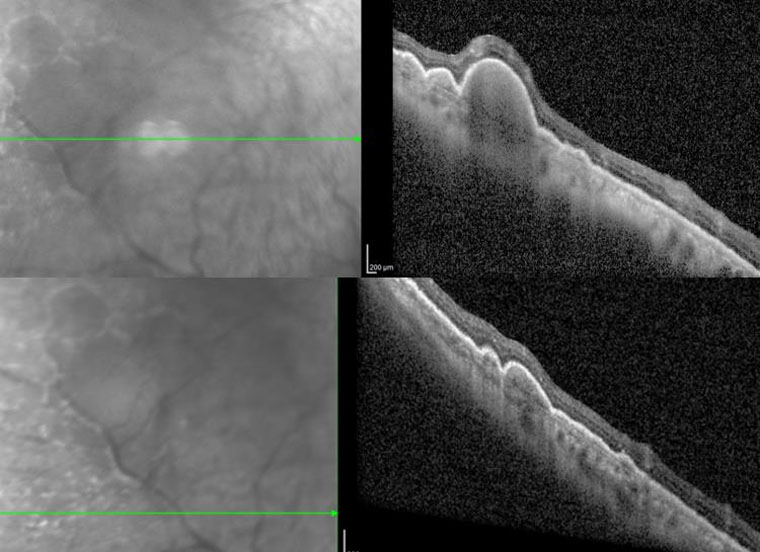

右眼OCT(光學相干斷層掃描)

郝玉華主任及其團隊仔細翻閱既往病例資料,完善相關眼科檢查,根據雙眼玻璃體內大量細胞、OCT提示視網膜外層結節樣病變和眼底隱約可見黃白色病灶的癥狀,高度懷疑雙眼眼內淋巴瘤合并中樞神經系統受累,經與患者及家屬詳細交代病情,決定行右眼診斷性玻璃體切除手術以明確診斷。